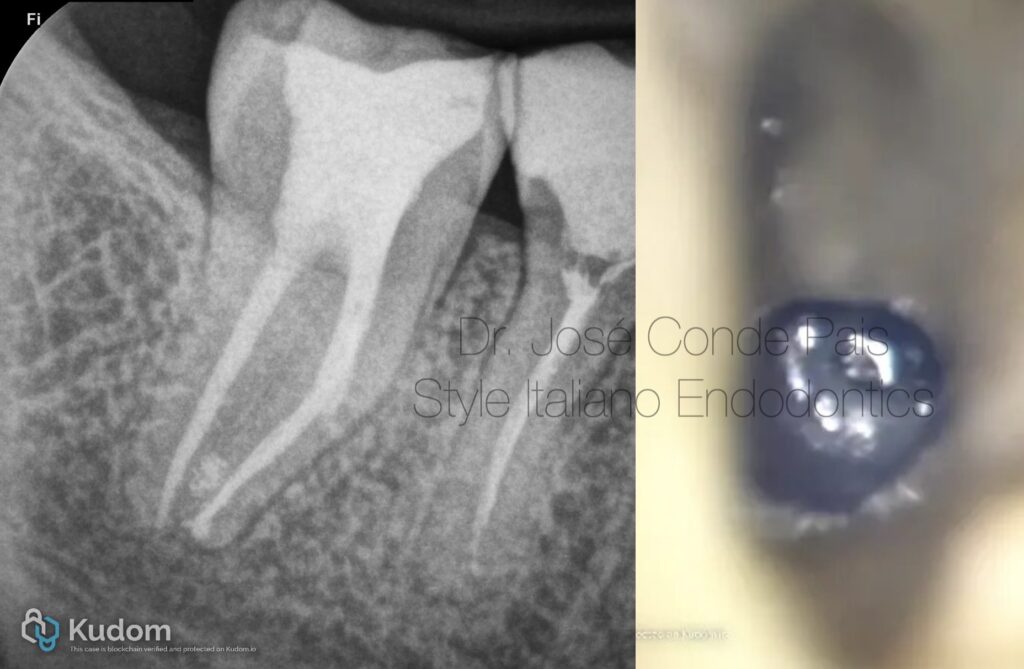

Fig. 1

37-year-old healthy patient referred for evaluation of tooth 37. Previous endodontic treatment complicated by a fractured instrument in the mesiobuccal canal.

Periapical radiograph revealed a retained fragment associated with apical pathology .